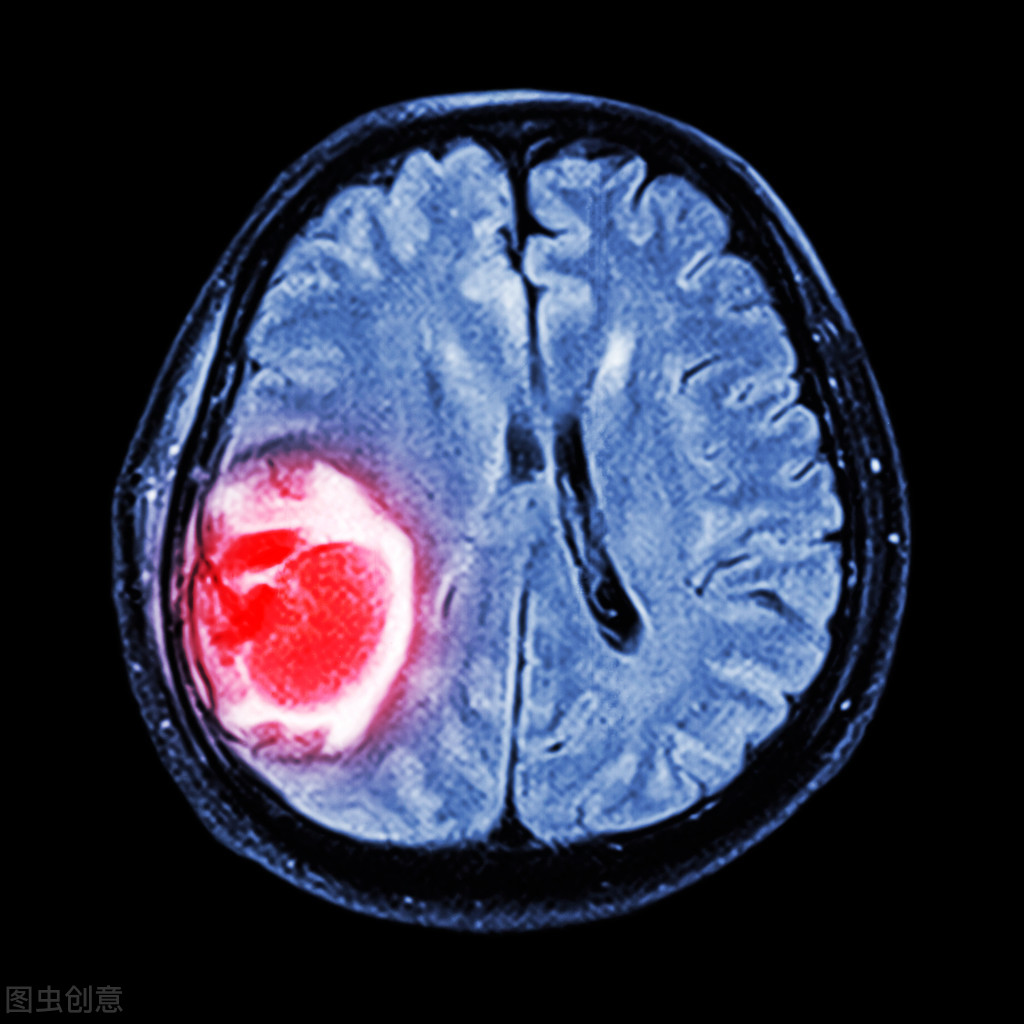

在我们日常生活中非常常可见的一种病症就是垂体瘤,它不仅会对患者的身体健康造成极大的伤害,同时也会严重影响病人的正常生活和工作,所以对这种病症有一定的了解显得尤为重要。有很多人不了解什么样的人容易得垂体瘤,其实它主要发生在中老年人之中,而在青少年之中较为少见。

1、垂体瘤是一种很常见的肿瘤,患病率大概在20%左右,每100个人就会有20个人有垂体瘤。不过,大部分垂体瘤都是无功能垂体瘤,不会引起身体不适,所以很大多数人可能终身都不会发现自己有垂体瘤。垂体瘤主要发生在老年人中,青少年相对少见。在各种类型的垂体瘤中,催乳素瘤最多,而且大部分患者都是女性;其次是生长激素瘤和促肾上腺皮质瘤。

3、垂体瘤是一组从垂体前叶和后叶及颅咽管上皮残余细胞发生的肿瘤。此组肿瘤以前叶的腺瘤占大多数,来自后叶者少见。据不完全统计,其中PRL瘤最常见约占50-55%,其次为GH瘤20-23%,ACTH瘤5-8%,TSH瘤与LH/FSH瘤较少见。无功能垂体腺瘤,占20-25%。垂体瘤约占颅内肿瘤的10%。垂体瘤大部分为良性腺瘤,极少数为癌。